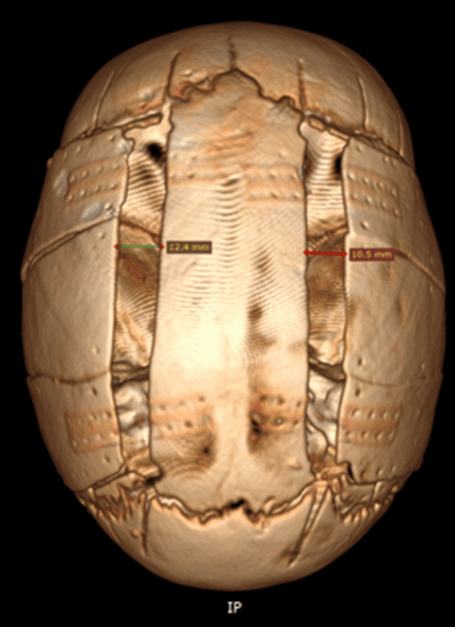

Рис. № 6 Брахиоцефалия

а) - до и после операции

б), в) - СКТ снимки после установки дистракторов.